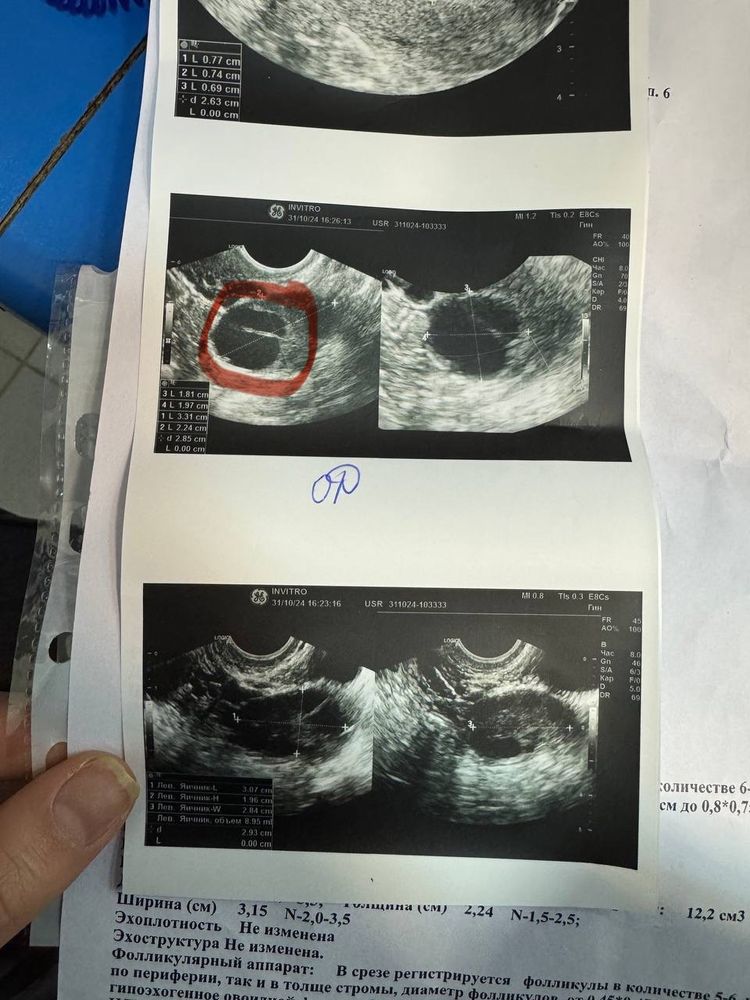

ЖТ нормальное или нет

Девочки,нужна ваша помощь. У меня всегда овуляция на 18ДЦ. Сходила на 17 ДЦ на узи и врач сказала что видно хорошое ЖТ и такое ощущение что овуляция была два дня тому назад. Очень странно мне показались снимки,скажите пожалуйста нормальное ли ЖТ смущает белая линия